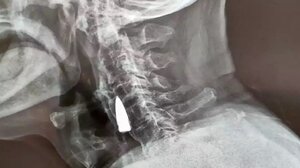

Απίστευτο: 95χρονος Κινέζος ανακάλυψε ότι ζούσε για 8 δεκαετίες με μια σφαίρα σφηνωμένη στον λαιμό του ΚΟΣΜΟΣ 20.11.2022Απίστευτο: 95χρονος Κινέζος ανακάλυψε ότι ζούσε για 8 δεκαετίες με μια σφαίρα σφηνωμένη στον λαιμό του